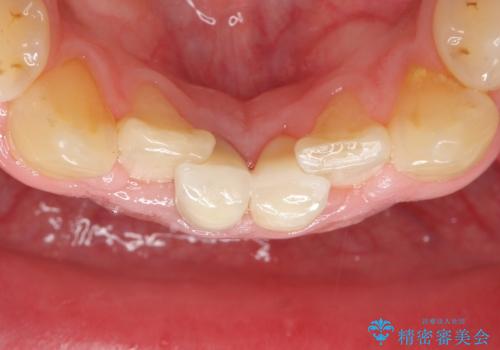

神経が死んでいる歯の根管治療を行った後、セラミッククラウンによる補綴治療を行いました。

比較的短期間(2ヶ月、来院回数:5回)で治療が終わったこと、また自然な仕上がりと使用感にご満足頂けました。

ジルコニアクラウン スタンダード